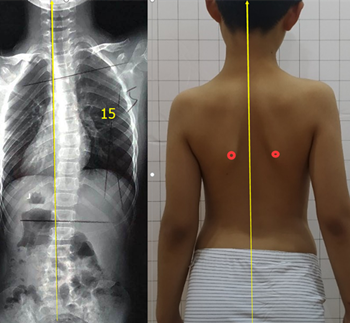

青少年脊柱側(cè)彎一旦被家長(zhǎng)發(fā)現(xiàn),應(yīng)積極治療,阻止側(cè)彎進(jìn)一步加重。但也有一些孩子,在發(fā)現(xiàn)脊柱側(cè)彎后,由于醫(yī)生判斷失誤,家長(zhǎng)不重視等等原因,沒(méi)有采取任何治療。發(fā)育期的孩子明顯增加較快,每個(gè)月基本增加1度。每年12度左右。

盡早展開(kāi)學(xué)校脊柱側(cè)彎篩查,在30度以內(nèi)發(fā)現(xiàn),最后可以治療到低于20度。如果這樣,對(duì)孩子的影響幾乎可以忽略。